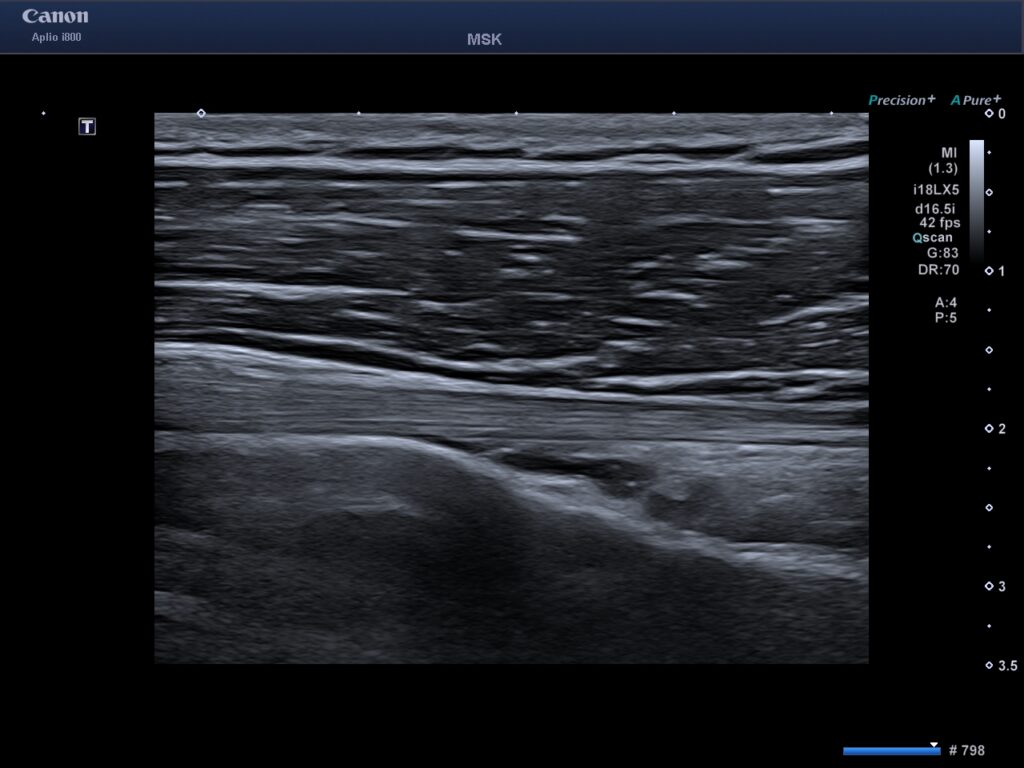

Att undersöka axeln med ultraljud är ofta det mest effektiva sättet att ställa en diagnos vid mjukdelsskador. Till skillnad från en vanlig röntgen ser vi senor, muskler, ligament och slemsäckar i realtid.

Vad kan man se vid en ultraljudsundersökning av axeln?

- Senskador (Rotatorcuffen): Vi ser om det finns delvisa eller totala bristningar (rupturer) i axelns viktiga senor som supraspinatus, infraspinatus och subscapularis.

- Slemsäcksinflammation (Bursit): Vi mäter vätskeansamlingar och förtjockningar i slemsäcken (subakromiella bursa).

När du kommer till oss i Göteborg börjar vi med en klinisk undersökning där vi testar din rörlighet och styrka. Därefter appliceras en gel på axeln och vi för ultraljudssonden över området. Bilderna visas direkt på en skärm där din behandlare förklarar vad som syns.